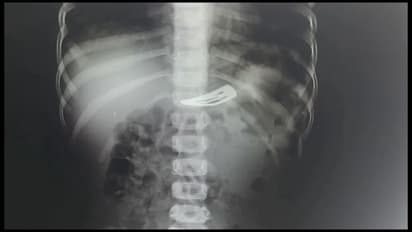

அதனைத் தொடர்ந்து உடனடியாக வீட்டிற்கு அருகில் இருந்த மருத்துவமனைக்கு அழைத்துச் சென்றனர். அங்கு குழந்தையை பரிசோதனை செய்த மருத்துவர் எக்ஸ் ரே எடுக்குமாறு கூறியுள்ளார். எக்ஸ் ரே எடுத்து பார்த்தபோது இரைப்பையில் ஹேர் கிளிப் இருந்தது தெரிய வந்தது. இதனையடுத்து திருவாரூர் ஜவுளிக் காரத் தெருவில் உள்ள தனியார் மருத்துவமனைக்கு அங்குள்ள மருத்துவர் பரிந்துரை செய்துள்ளார். பெற்றோர்கள் அங்கு குழந்தையை அனுமதித்துள்ளனர்.

இதனையடுத்த தனியார் மருத்துவமனையின் அறுவை சிகிச்சை நிபுணரான மருத்துவர் சுந்தர் என்பவர் குழந்தையை பரிசோதித்து விட்டு மயக்க மருந்து நிபுணர் மருத்துவர் ஸ்டாலின் உதவியுடன் அறுவை சிகிச்சை இன்றி என்டோஸ் கோபி மூலம் குழந்தைக்கு எந்த வித பாதிப்பும் இன்றி குழந்தையின் இரைப்பையில் உள்ள ஹேர் கிளிப்பை பத்து நிமிடங்களில் அகற்றியுள்ளார்.